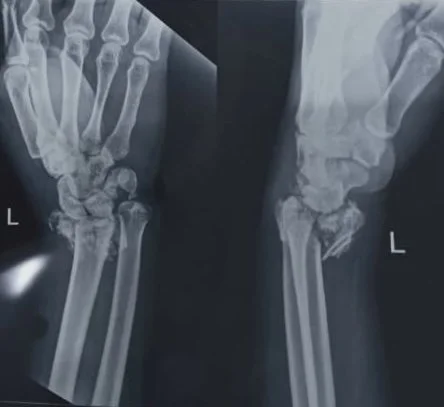

His right leg and left wrist were fractured, and he had some scratches near his right eye. Thankfully, because he was wearing a helmet, he did not have any serious head injuries.

The doctors placed a permanent steel rod in his leg and said it should heal completely. They will have to do a follow-up on his wrist next week to see if it is healing correctly or if he will need another operation.